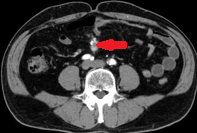

Contrast-enhanced CT demonstrates soft-tissue lesion in left carotid sheath (Courtesy Dr. V. Penopoulos)